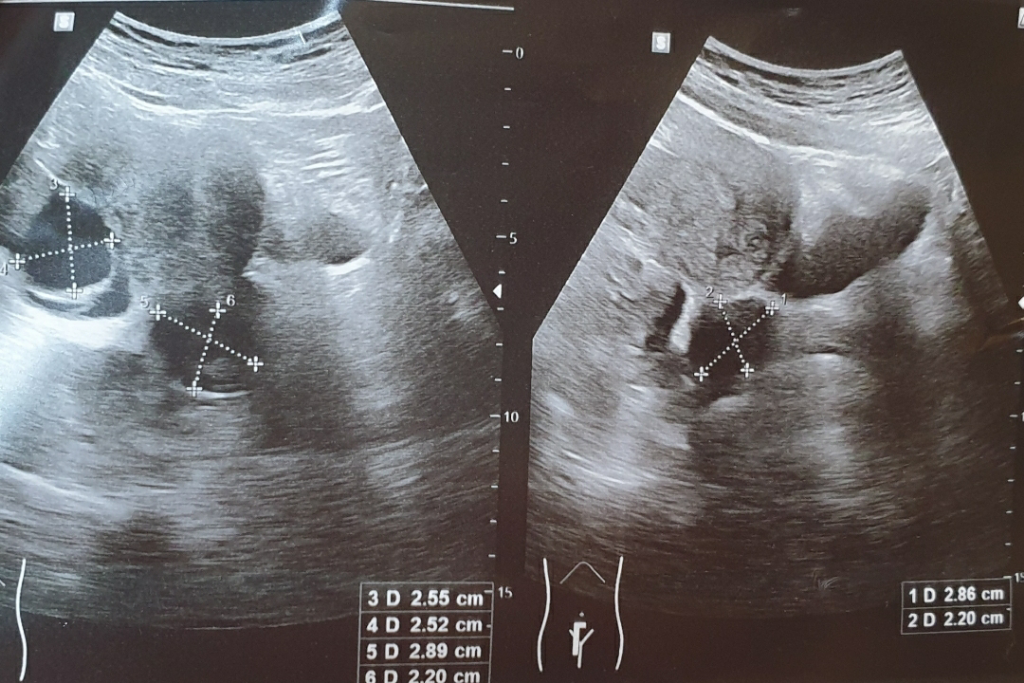

내과를 가서 복부초음파 했는데요 (아래 사진) 아랫배쪽에 물혹이 두개가 보이신다고 하시더라구요. 하나는 난소물혹인데 하나는 자궁경부쪽 으로 보인다고 하셨어요.

그래서 산부인과에 갔더니 난소물혹 하나만 3센치 있고 . 내과에서 다른물혹이 있다고 하시던데요 말씀드리니 모르겠다고하시더라구요.

아이 아랫쪽 물혹은 어디에 있을가능성이 있을까요. 혹시 대장혹이나 암 방광혹이나 암 신장이나 다른문제가 있을수도 있을까요?

• 1번 째 사진